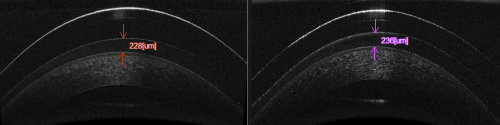

Cue the deafening sounds of aghastment. Fitting an already heathen device to a previously altered cornea? You must be mad! Indeed, in the main orthokeratology ‘bible’; John Mountford’s Orthokeratology: Principles and Practice published back in 2004, there is no mention of fitting orthoK to the post-LASIK cornea (although John is working on a new edition which may address this). A pubmed search shows no articles about orthoK on a post-LASIK cornea. Despite this many experienced orthokeratologists around the world practice ortho-K on the post-LASIK cornea with excellent results. I personally believe there is no more harm in fitting orthokeratology lenses to a lasered cornea than to a virgin example. It is the understanding of most orthokeratologists that the refractive effect of orthoK comes about due to modification of the epithelial cells of the cornea, although the jury is still out in some circles. The following OCT of a patient of mine using orthoK lenses for high myopia illustrates this by showing the thinned epithelium centrally and thickened layer para-centrally. The stroma remains relatively uniform. In contrast all forms of laser refractive corneal surgery involve permanent modification to the stroma of the cornea. The mechanism of refractive change in these two modalities are mutually exclusive. In post-LASIK orthoK the main challenge comes with designing the back surface of an orthokeratology lens to firstly fit the para-central cornea safely and comfortably, and secondly remodel the central epithelium in a way to correct the refractive error. Let’s look at an example:

Anterior OCT showing the thickness profile of the corneal epithelium in myopic orthokeratology. Note this well-fitted lens does not touch the cornea within the treatment zone.